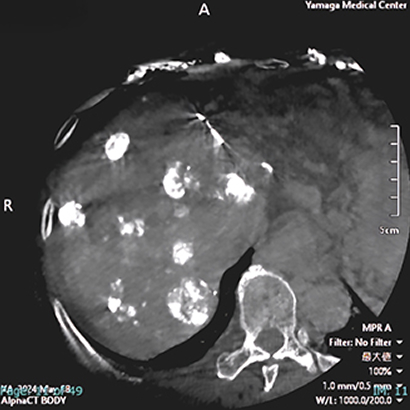

また、CTの更新に伴い3次元画像解析ワークステーションsynapseVINCENTを最新版にバージョンアップしました。 FUJIFILM独自のAI技術を搭載し、自動抽出機能が充実したことで、整形領域をはじめ、冠動脈解析、肝切除術前シミュレーション、大腸癌術前CTcolonographyにおいて、より短時間で高精度な3D解析ができるようになりました。

CTの検査画像例